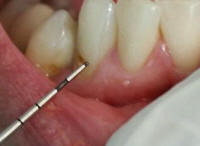

Sonda